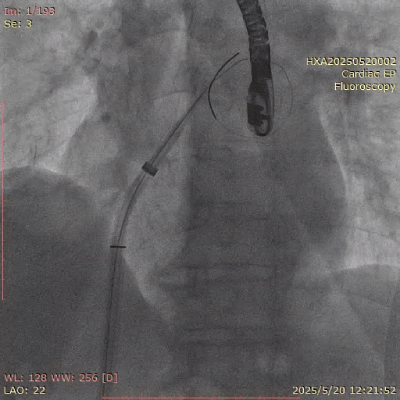

在经股静脉途径的TEER手术时,房间隔穿刺是一个很重要的基础步骤。有时候房间隔组织较韧较厚(多见于房间隔短穿刺位置需要靠后,或者外科房间隔修补术后),穿刺针通过之后要通过导引大鞘(GC)存在着较大困难,若强行推送大鞘可引起房间隔撕裂到左心房顶引起灾难性心包填塞。传统做法时使用外周球囊对房间隔进行扩张,但是不是每个导管室都常规配备外周球囊,且使用过大球囊仍可引起房间隔撕裂风险。我们提供了一种更简洁的方式,即使用导引鞘内芯和房间隔穿刺鞘两个管子(双管齐下)同时扩张房间隔穿刺口,再推送导引大鞘通过房间隔,无需额外器械,操作简单高效且安全(图1-4)。

图2. 从房间隔穿刺鞘里送入两根Lunderquist 超硬导丝